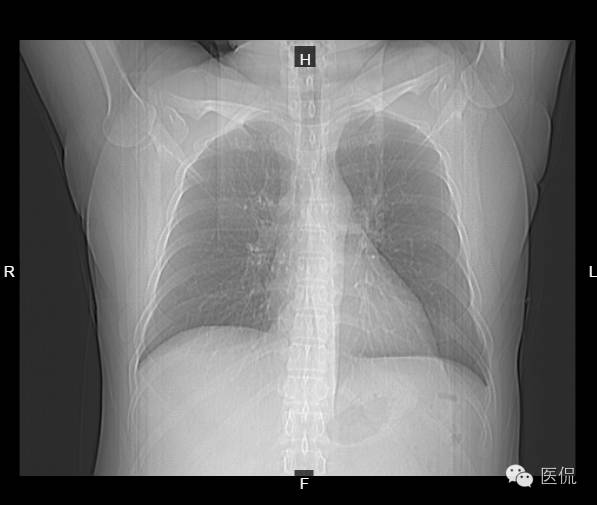

患者信息:男,37岁,体检

检查部位:ch

检查方法:胸部CT平扫

影像所见:

CT平扫胸廓对称,肺窗显示两肺纹理清晰,走向分布无异常,肺实质未见渗出或占位性病变。纵隔窗显示两肺门无增大,气管支气管通畅,纵隔未见肿大淋巴结,心脏及大血管走行未见明确异常,胸膜、肋骨及胸壁软组织未见异常。肝实质密度减低,CT值46HU。

诊断意见:

1、胸部CT扫描未见异常。

2、脂肪肝。